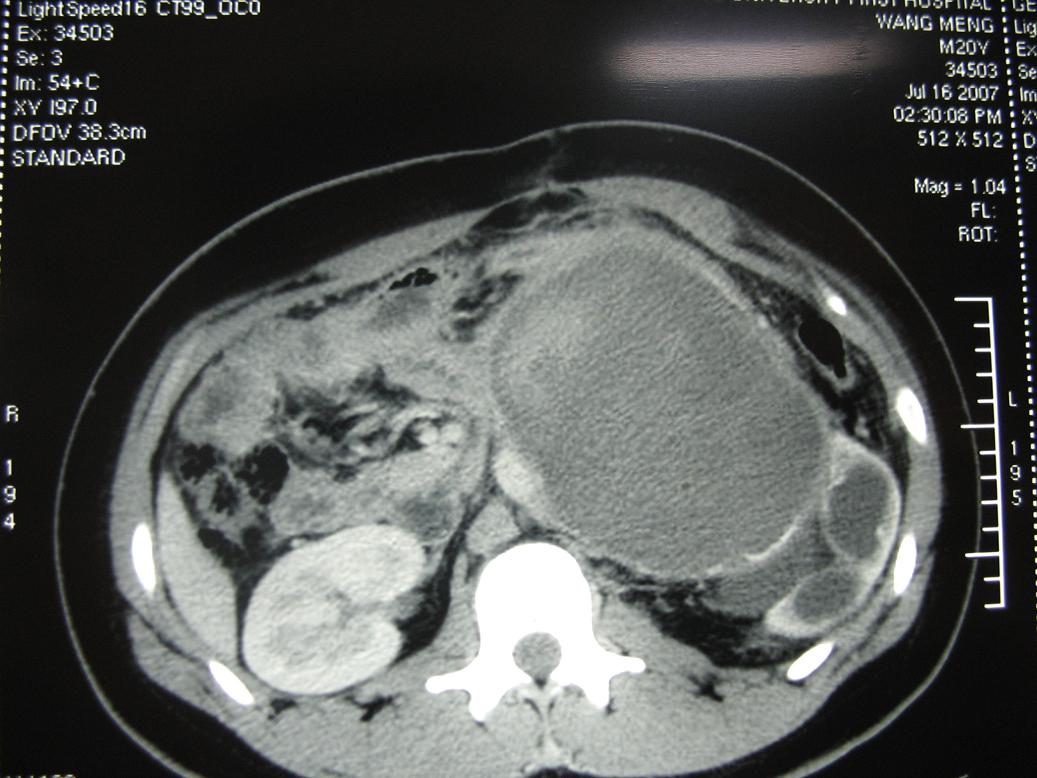

m20,发现腹部肿物二月.

2、左侧腹膜后囊实性占位性病变,有完整包膜,周围脏器及血管呈受压移位改变,左肾积水,肾实质变薄,增强扫描示病变包膜有强化,因图片太少,实性部分是否强化不好判断。

3、诊断:结合病人年龄,左肾改变考肿虑为输尿管受压肾积水时间长,左肾实质萎缩,病变未见明显外侵征象,本人首先考虑为神经源性瘤囊变可能性大。

1)考虑左侧腹膜后恶性肿瘤(肉瘤?)伴瘤体内出血。2)左肾积水。

结果收到,肿块较大,密度不均,实性部分有强化,包绕腹主动脉推挤左肾,左肾集合系统受压改变,病灶长轴与腹主动脉平行,支持副神经节瘤,但不典型。